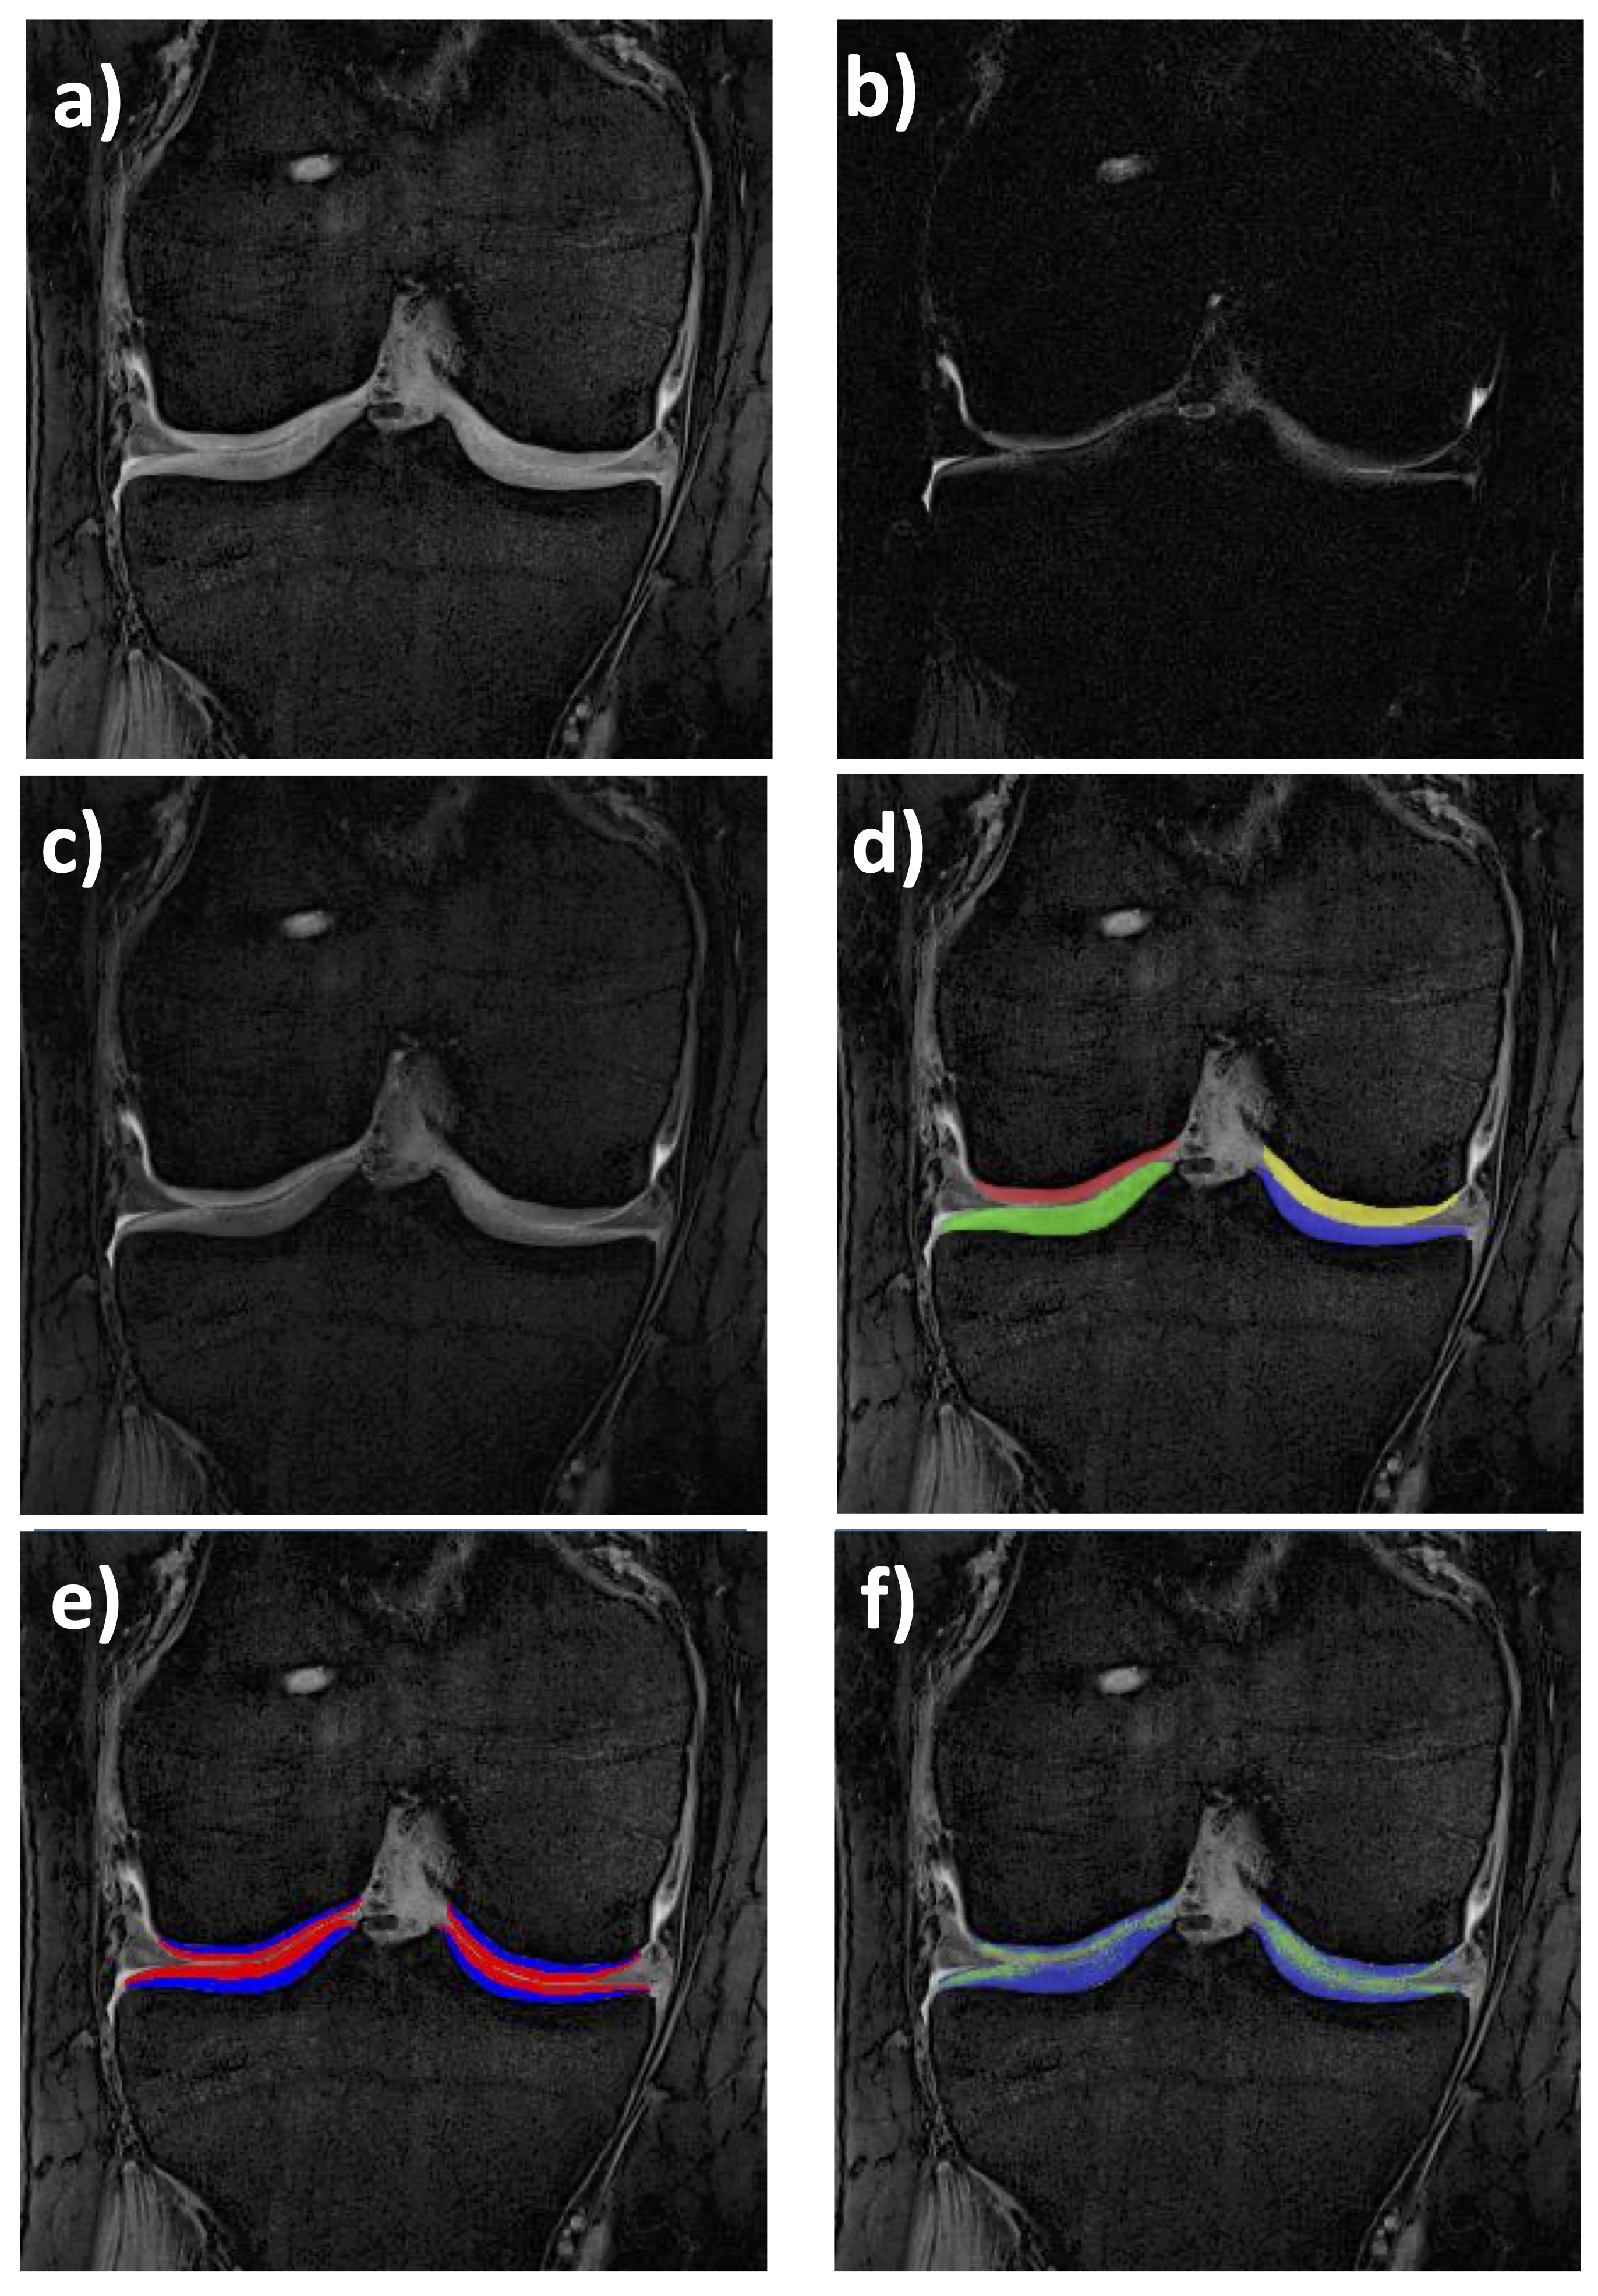

Figure 2. Coronal quantitative double-echo steady-state (qDESS) MRI of the femorotibial joint (FTJ): a) First echo (4.85 ms); b) Second echo (12.14 ms); c) Merged qDESS image (a and b) with mixed contrast; d) Cartilage segmentation of the medial (MT) & lateral tibia (LT), and medial (cMF) & lateral femur (cLF); e) Cartilage segmentations of the four FTJ plates showing the superficial & deep layer (50% of the total local thickness, respectively); f)T2 map (only cartilage T2 is shown, no other structures)

From an MR image acquisition perspective, T2 maps can be generated by various spin echo or gradient echo techniques [4]; the most widely used is 2D multiple-echo spin-echo (MESE – Fig. 1). MESE uses 4-8 different echo times (TEs) to derive T2 on a voxel-by-voxel basis. Yet a more versatile 3D gradient echo-based sequence has recently been proposed, i.e. quantitative double echo at steady state (qDESS – Fig. 2) in combination with water excitation [23–28]. qDESS generates two echoes per repetition time (Fig. 2), separated by a spoiler gradient. An image is formed from each echo, and T2 can then be computed from changes in voxel signal intensity between the two sets of images. The image formed from the first echo displays mixed T1/T2 contrast, whereas the image formed from the second echo exhibits contrast with contributions from both T2 and diffusion effects. Conventional DESS[24, 29, 30] combines data from both echoes (Figs 2 a, b) to generate a single (fused) image with mixed T1-/T2-contrast (Fig. 2c), enabling morphometry but not relaxometry (T2). However, with a modification of the gradient fields and images from both echoes stored separately (qDESS), a voxel-by-voxel fit can generate the desired high-resolution T2 map (Fig. 2f). This approach has been validated versus single echo spin echo T2, the gold standard for this type of measurement [23–27].

As alluded to in the introduction, a relatively novel quantitative double echo steady state (qDESS – Fig. 2) sequence with water excitation can image knee cartilage with high resolution, low acquisition time, superior contrast-to-noise, and - in contrast to MESE - without “missing” much of the radial (deepest) cartilage layer [66]. This is important, because several of the above studies have suggested that the greatest sensitivity of T2 to OA related changes is in the deep layer. Heule et al. (21) was one of the first to propose qDESS rather than MESE for T2-estimation, to enable simultaneous extraction of relaxometry and morphology cartilage measures. Please note that the benefit is not only a markedly reduced acquisition time for the comprehensive study of cartilage health, increasing the well-being and compliance of patients, but that further only a single segmentation is necessary for extracting T2 and thickness, facilitating the cartilage analysis workflow greatly and reducing time and cost required for the analysis. The above authors introduced a novel post-processing approach to overcome T1-related bias for rapid DESS-based T2 quantification in the low flip angle regime by a rough global T1 estimator and a golden section search (21). Chaudhari et al. then used qDESS and compared both the cartilage thickness and cartilage T2 (as well as meniscus T2 and MOAKS semi-quantitative scores) measures with those from gold-standard methodologies in 15 volunteers and 15 OA patients, respectively [23]. Note that the difference in imaging time between a T2-standard qDESS (0.62 mm in-plane resolution: 2:37 min) and a morphometry-standard qDESS (0.31 mm: 14:20 min) was substantial, albeit still low with the combined imaging time of a non-quantitative standard DESS for morphometry, and MESE in the OAI (21 min scan time per knee combined). Therefore, the authors optimized target sequence (qDESS-EXP) readout bandwidth (642 kHz) to reduce the readout duration, while achieving high spatial resolution. Further, the target qDESS employed a 384x512 matrix (in readout and phase-encode directions) to maintain short repetition (TR) and echo times (TE), to achieve high SNR for T2-relaxometry, and the high in-plane resolution desired for morphometry, at an acquisition time of 4:48 mins (16). Applying this sequence, test-retest precision of cartilage thickness of <1%, and that of T2 <2%, with high agreement with gold standard measurement. Using this type of qDESS, the same authors set out to demonstrate a rapid pulse sequence that can be implemented across different MRI vendors with harmonized parameters that yields highly consistent cartilage morphometry and T2 relaxometry outcomes [87]. The left and right knees of 5 participants were imaged (including test-retest) using a 3T GE Signa Premier (18 channel transmit/receive coil), and a 3T Philips Ingenia (16 channel transmit/receive coil) yet only with 3 mm slice thickness [87]. Scan-rescan repeatability was high for all metrics with a maximum variability (CV%) of 2.1% for morphometry, and 4.4% for T2 relaxometry. At inter-vendor comparison, cartilage thickness and volume variation were moderate (about 4.0%), but that for cartilage T2 was relatively high (up to 13%). Inter-vendor T2 left-right asymmetry repeatability between both knees did not differ significantly between the two vendors (p=0.11)(81).